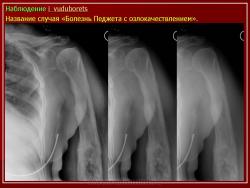

Доктор медицинских наук, профессор   Берченко Геннадий Николаевич

Вторичная остеосаркома может развиваться на фоне болезни Педжета, остеобластомы, множественных врожденных экзостозов. В работе выделено 3 остеосаркомы на фоне болезни Педжета, 3 - постлучевых остеосарком и 1 - остеосаркома костей таза при болезни Оллье.

Макроскопическая картина выявляет границу саркоматозного компонента, особенно если разрушена кортикальная пластинка пораженной кости.

Микроскопическая картина остеосаркомы при болезни Педжета - удается выявить мозаичные структуры цементирования в окружении веретеноклеточного саркоматозного компонента, гистологический вариант остеосаркомы и степень дифференцировки опухоли отличается от случая к случаю. В наших наблюдениях все три остеосаркомы обладали признаками низкой степени дифференцировки с фокусами патологического остеоида.